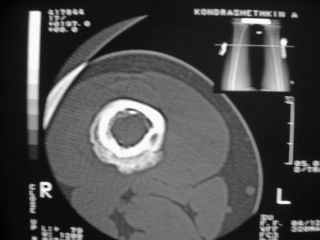

Анамнез практически никакой: в следствие травмы (растяжение связок коленного сустава) от 07.11.2004 выполнены Rg-граммы в травмпункте и обнаружено опухолевидное образование. Первичные Rg-граммы я не публикую, так как они заметно худшего качества, да и динамики за прошедшие три недели не отражают. Болевой синдром купирован в течение трёх дней. В настоящий момент мальчика ничего не беспокоит. Ходьба не нарушена, опухоль пальпируется с трудом по задней поверхности в н\3 правого бедра, пальпация безболезненна, объем движений в суставах правой нижней конечности полный и симметричный. Кожа над опухолью не изменена. В нашей клинике проведено дополнительное обследование: общие анализы крови и мочи, биохимия крови без особенностей. Выполнены Rg-граммы на цифровом Siemens обычные и продольные томограммы срезами 3-5 мм, а также компьютерная томография поперечными срезами по 5 мм. Прошу обратить внимание, что на приведённых томограммах видны две полости 10х15 мм и 15х60 мм. Также имеются два опухолевидных образований наслаивающихся друг на друга: уплощённое и вытянутое 10х100 мм и элипсовидной формы 15х30 мм. Это хорошо заметно на фото a_1.jpg c_1.jpg и d_1.jpg. Плотность внутри полостей 125% от плотности костномозгового канала, плотность наружного опухолевидного образования 55% от плотности кортикального слоя. Также отмечается линия перелома по центру наружного опухолевидного образования. Исходя из полученных данных мнения в плане диагноза несколько разделились от 1)сочетания кортикальной фиброзной дисплазии и латентно протекавшего маршевого перелома н\3 правого бедра до 2)остеосаркомы. В отношении первого варианта не сходится отсутствие клиники при переломе такой крупной кости как бедро, второй вариант вообще оставлю без комментария, ибо некомпетентен. Хотелось бы услышать мнения коллег, с удовольствием ознакомлюсь с любыми предположениями и замечаниями. С уважением, Александр Е. Клоков Отделение детской ортопедии и травматологии БСМП г. Мурманска.